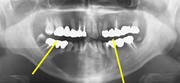

下顎骨の腫瘍で下顎を切除し(写真左)、切除したところを腰骨で再建し(写真中央)、インプラントを支えにしたブリッジ(写真右、白い部分)でかめるようにした症例のエックス線写真